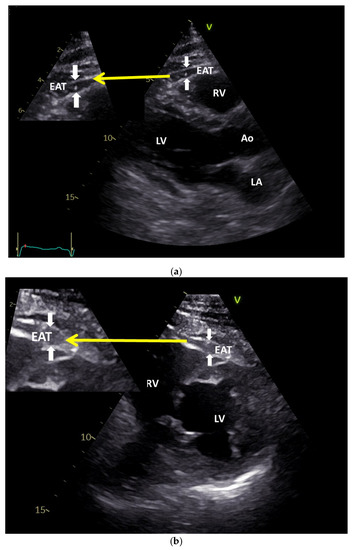

3.3. Non-Invasive Measurement of Epicardial Fat: Ultrasound, Computed Tomography (CT), and Magnetic Resonance Imaging (MRI)